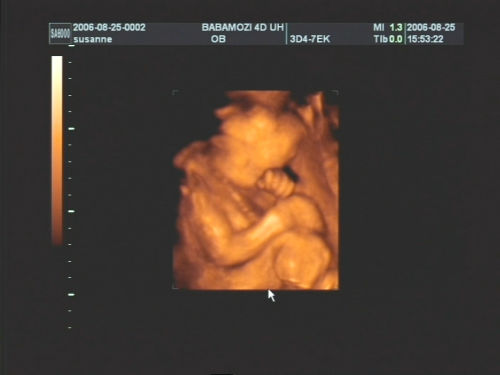

Pár kép:)

És akkor jöjjenek a képek:

Nem tudtam betelni velük,és nem tudtam választani közülük,azért van ilyen sok:

Kép Olyan kis szégyellős volt a drága,hogy állandóan takargatta a szemeit:Kép